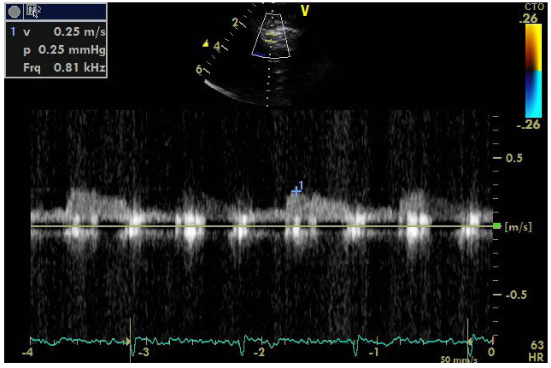

An additional element is the localization of the stenosis in the initial part of renal vessel, as opposed to FMD that commonly affects the middle and peripheral portions. The sudden deterioration of renal function within a short period of time also advocates for atherosclerosis as the FMD has a slower course. It is noted that atherosclerosis may lead to complete abstraction/thrombosis over time, rarely occurring FMD. Finally, the immunological test performed to rule out vasculitis was negative. Renal arteriography indicated a 99% stenosis to the left and the patient underwent a successful stent implantation. After angioplasty, blood pressure returned to normal and the patient did not receive any medication. It is worth noting that despite the presence of stage III hypertension and the underlying disease, the patient did not show signs of diastolic dysfunction in the Doppler (Figures 8–10), nor any signs of hypertrophic left ventricle in ECG.  Not a patient with long-standing uncontrolled hypertension. Moreover, to stress echocardiography with doboutamine there were no wall motion abnormalities, while coronary flow reserve was normal (CFR LAD=2.2) (Figure 11A & 11B).

Figure  10A Coronary flow reserve LAD, basal flow.

Figure  10B Coronary flow reserve LAD, hyperemic flow after adenosine infusion.